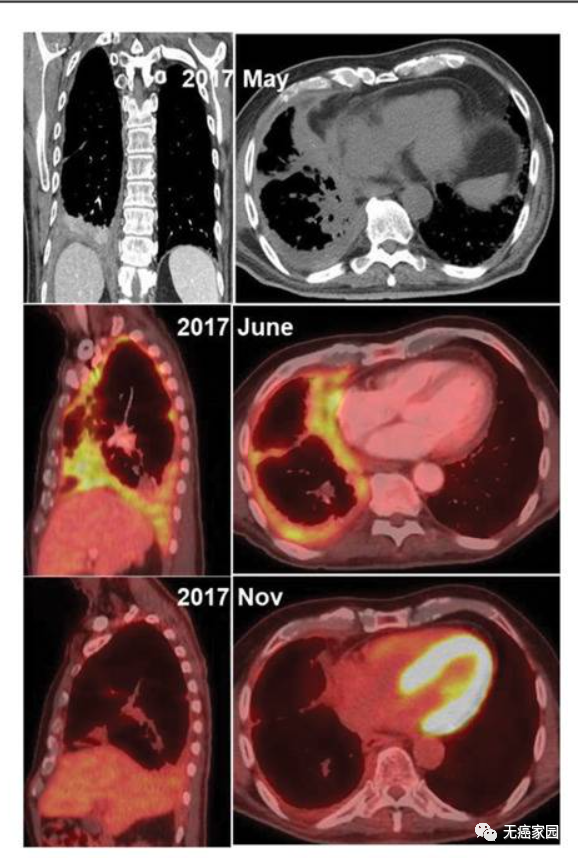

患者A:一名 76岁的上皮样恶性胸膜间皮瘤患者仅使用 CAR-T细胞疗法就使靶病变减少28%(如图),随后在PET扫描和CT扫描上出现完全代谢反应,帕博利珠单抗治疗后靶病变减少78%(如图),这种反应持续了26个月。患者的血清SMRP(间皮素相关蛋白)水平保持在基线水平,患者功能保持良好。

患者A的治疗反应

患者B:一名双相恶性胸膜间皮瘤的72岁患者,观察到PET扫描和CT扫描的部分缓解相似的完全代谢反应(mRECIST;目标病变减少 40%),如图所示。这种反应在没有其他治疗的情况下持续了16个月,患者功能正常,体重增加并保持不变,血清SMRP水平也保持在基线水平。

患者B的治疗反应